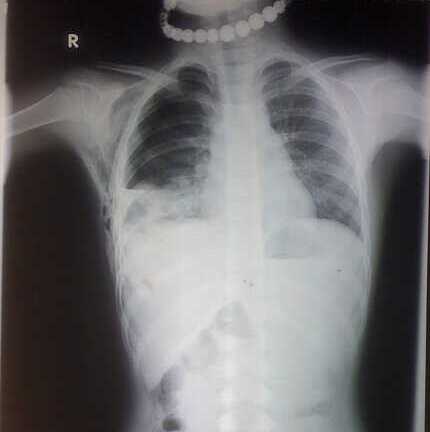

(VTC News) – Bị trâu húc trong khi cùng bạn đi ngang qua cánh đồng, cháu X bị chấn thương nặng vùng ngực, người xây xát, khó thở, tràn máu, tràn khí màng phổi.